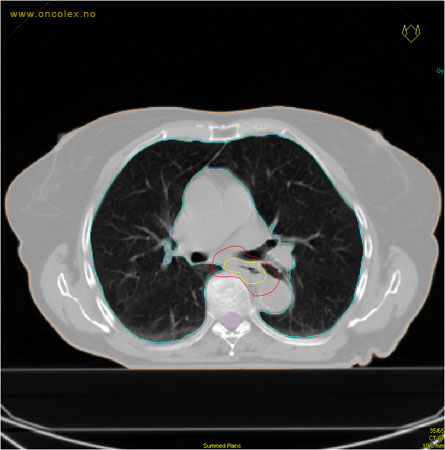

Det gjøres en CT undersøkelse for bildeopptak i en dedikert CT-maskin, helst med kontrast./p>

Strålefeltet innstilles basert på  CT bilder av området.

Bilder til planlegging tas på simulatorenheten. Det er viktig at pasienten ikke har smerter eller er urolig slik at hun/han klarer å ligge stille på ryggen den tiden som er nødvendig (20-30 minutter). Eventuelt gis smertestillende og/eller beroligende medikamenter. Undersøkelsesbordet er flatt med kun en tynn madrass. Pasienten får en standardisert pute under knærne og stor pute under hodet. Armene holdes opp langs hodet. Dette leiet er nødvendig siden det er identisk med det som brukes på behandlingsapparatene.

Intravenøs kontrast brukes rutinemessig. Pasienter med diabetes som bruker medikament av metformin-type, må ikke ta disse de siste 2 døgn før planleggingen. Inntegning, utarbeidelse av strålefelt, nødvendige justeringer og overføring av data og bilder til behandlingsapparatet tar vanligvis 10-12 dager.